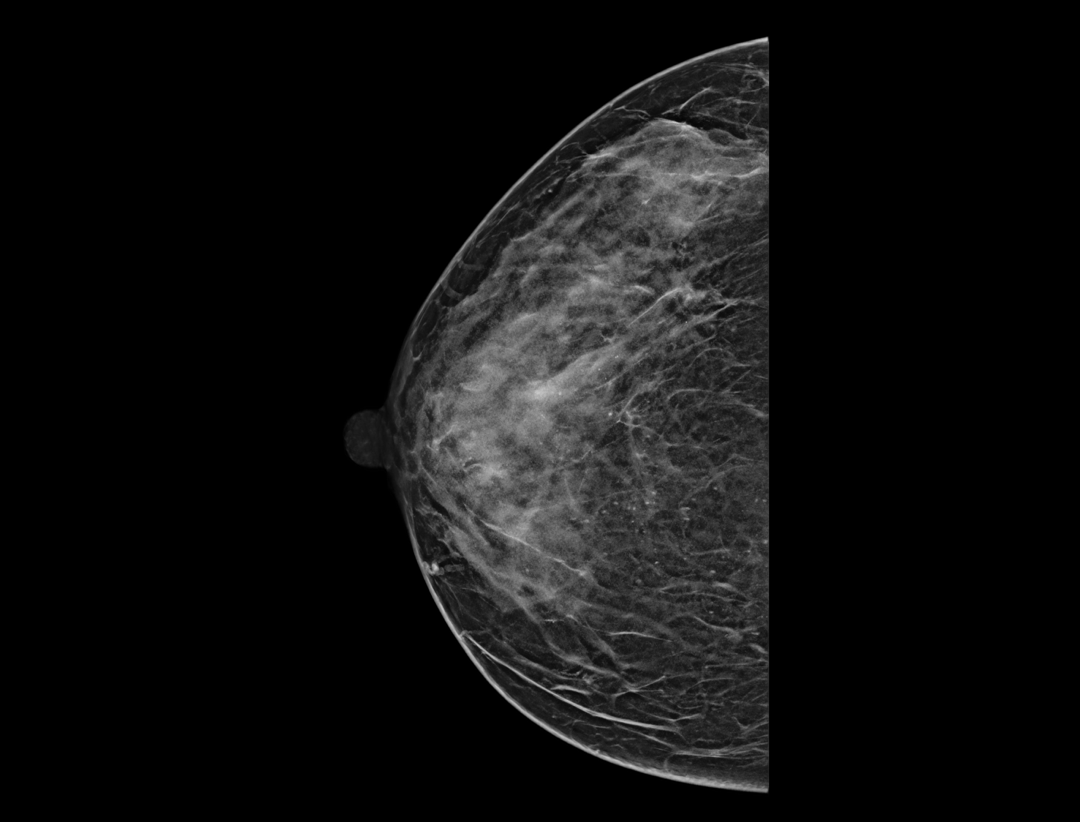

智能病灶定位*

快速在同一体位不同图像类型中精准定位感兴趣可疑区域,缩短阅片时间,提高效率。